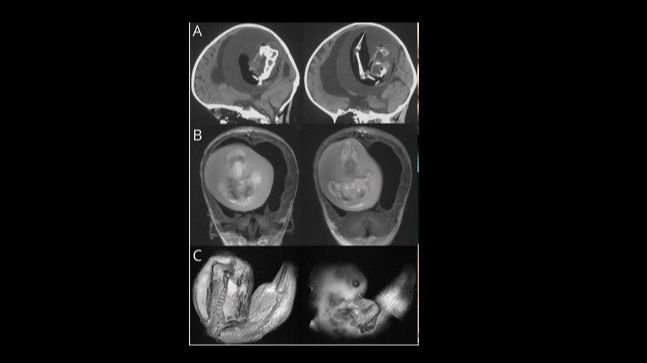

Una investigación de la Universidad de Fudan en Shanghái (China) ha informado de la intervención quirúrgica de una niña de 1 año a través de la cual se le extrajo el feto de su hermano, una anomalía clínica conocida como "fetus in feto" o "gemelo parásito".

El estudio fue publicado en la revista 'Neurology', y explica que la masa extirpada en la cabeza de la menor era un "gemelo diagnóstico monocriónico malformado".

Esta masa en la cabeza de la menor indica que en el útero de la madre ambos fetos compartieron la misma placenta. Sin embargo, tenían sacos amnióticos separados.

Normalmente el "gemelo parásito" se advierte como una masa en el abdomen del otro feto, en los tejidos que recubren la pared abdominal. En esta ocasión, el feto malformado apareció en el cerebro de su hermana, durante un proceso de desarrollo denominado 'plegamiento de la placa negral'.

En la intervención quirúrgica se observó que el feto mostraba indicios claros de desarrollo, ya que poseía columna vertebral, dos huesos de la pierna (fémur y tibia) e incluso dedos en las extremidades superiores.